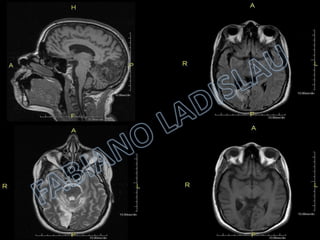

SAG T1 COR TFS AX T2 PROPELLER ENCEFALOMALÁCIA GLIOSE AX T2 FLAIR